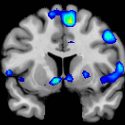

La exploración de fMRI de los sujetos participantes en el estudio muestra regiones del cerebro que se vuelven activas cuando los participantes tienen una experiencia espiritual, incluyendo un centro de recompensa en el cerebro, el núcleo accumbens, un grupo de neuronas del encéfalo a las que se atribuye una función importante en el placer y el sistema de recompensa.

Basados en las exploraciones de fMRI, los investigadores descubrieron que los sentimientos espirituales activan el núcleo accumbens, una región crítica del cerebro para procesar la recompensa. El circuito de recompensa es un grupo de estructuras neuronales del cerebro relacionado con el deseo, el placer y el refuerzo positivo.

Además de los circuitos de recompensa del cerebro, los investigadores descubrieron que los sentimientos espirituales estaban asociados con la corteza prefrontal media, una región cerebral compleja que se activa mediante tareas que incluyen valoración, juicio y razonamiento moral. Los sentimientos espirituales también activaron las regiones cerebrales asociadas con la atención focalizada.